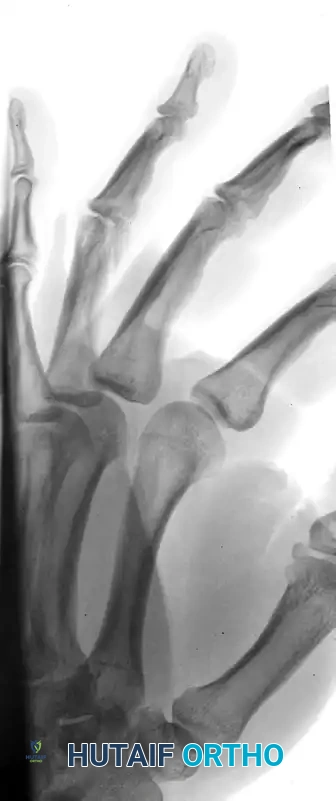

The following radiographs demonstrate a complex, three-part displaced intra-articular fracture of the proximal phalanx in a 27-year-old man. The articular surface is significantly disrupted, necessitating open reduction.

FIGURE 67-41 A: Preoperative anteroposterior radiograph demonstrating the intra-articular split.

FIGURE 67-41 B: Preoperative oblique radiograph highlighting the displacement and articular step-off.

FIGURE 67-41 C: Preoperative lateral radiograph showing the volar subluxation tendency.